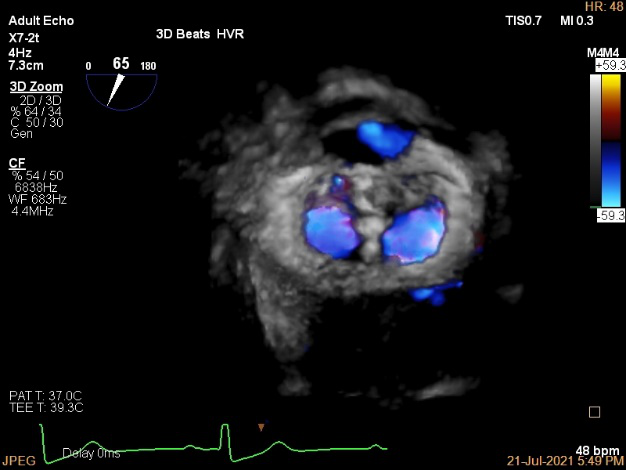

3D MV View

3D-color MV view:血流主要来源于2区近3区

Qlab软件勾画估测瓣口面积约:6.16cm²

3D视图打开夹子

3D视图下调Rotate,定位2区

3D视图下观察二尖瓣双孔形态

3D-color:残余少量返流